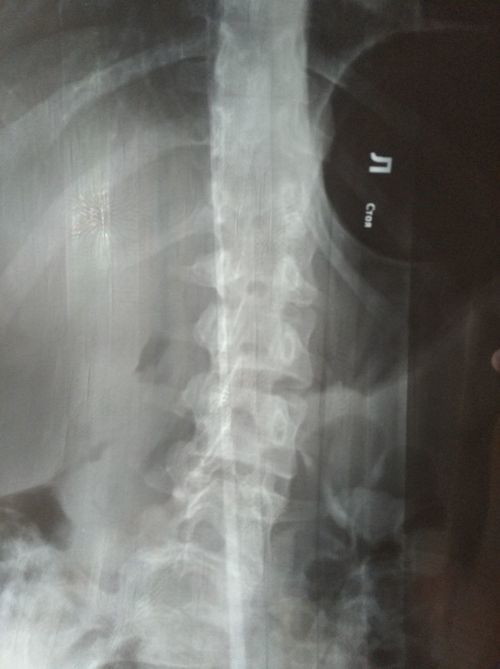

сколиоз является противопоказанием к эпидуральной анестезией? можно ли в моем случае ее провести. рентген сделан в разных проекциях. фото прикрепляю.